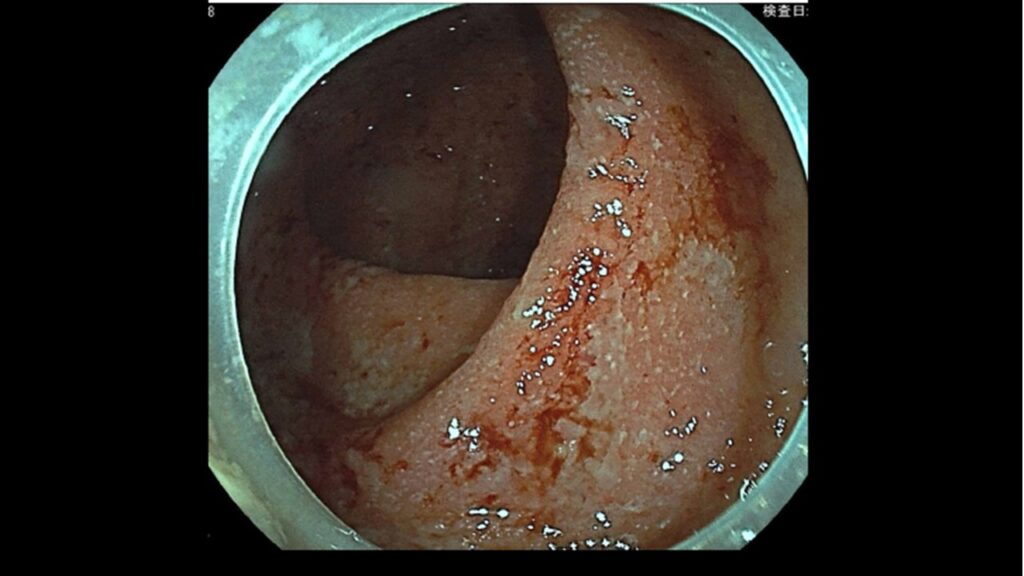

精密検査のため、当院にて**大腸内視鏡検査(大腸カメラ)を実施しました。 内視鏡で直接観察すると、本来見えるはずの粘膜の血管が見えなくなっており、全体的に赤く腫れ、ただれ(びらん)が広がっていました 。検査中の組織採取(生検)の結果、診断は「潰瘍性大腸炎」**という国が指定する難病であることが判明したのです。